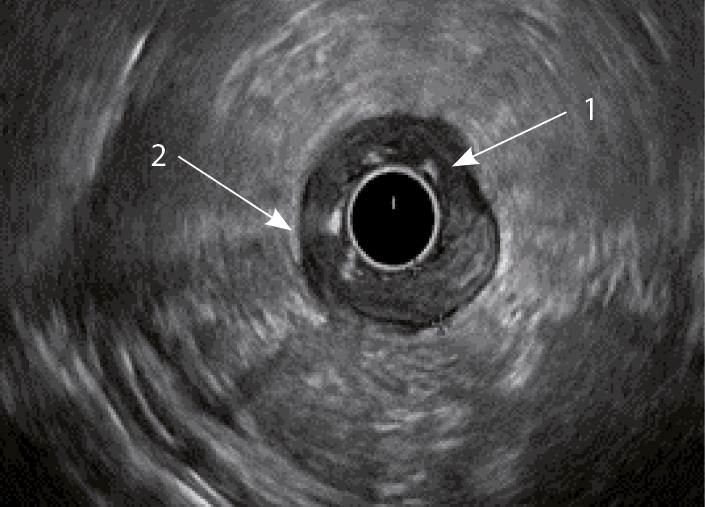

Рис. 3. Эндосонографическая картина толстой кишки при язвенном колите; 1 – утолщение слизисто-подслизистого слоя; 2 – утолщение стенки толстой кишки

Кишечная стенка статистически значимо чаще утолщалась за счет слизисто-подслизистого слоя при ЯК, чем при БК: в 82 и 7,14% соответственно; диагностическая чувствительность данного признака была 82%, а специфичность – 93% (табл. 1). При БК изменение стенки толстой кишки за счет трансмурального утолщения выявлялось статистически значимо чаще (68%), чем при ЯК (9%) (чувствительность 68%, специфичность 91%). Статистически значимых различий в частоте изменений мышечного слоя кишки отмечено не было. Только при БК в 68% случаев отсутствовала дифференцировка слоев кишечной стенки в фазе обострения (чувствительность и специфичность признака составили 68 и 100% соответственно) (см. рис. 4). При ЯК на фоне «смазанности» слизисто-подслизистого слоя у всех больных можно было визуализировать мышечный и серозный слои (см. табл. 1, рис. 3).